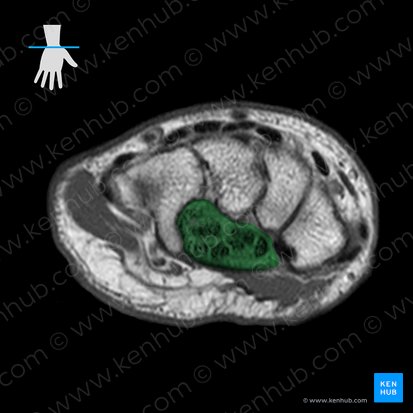

Die Handwurzel (Carpus) ist der proximale knöcherne Anteil der Hand und zählt zusammen mit der Mittelhand (Metacarpus) und den Fingern (Digiti) zum Handskelett.

Die Handwurzel besteht aus zwei Reihen unförmiger, kleiner Knochen, die dicht gepackt und durch nahezu unbewegliche Gelenke miteinander verbunden sind.

In der proximalen Reihe liegen das Os scaphoideum, Os lunatum, Os triquetrum und das Os pisiforme.

Die distale Reihe wird durch das Os trapezium, Os trapezoideum, Os capitatum und Os hamatum gebildet.

Man kann die Handwurzelknochen einer proximalen und einer distalen Reihe zuordnen.

Die proximale Reihe besteht aus (von radial nach ulnar):

- Os scaphoideum (Kahnbein)

- Os lunatum (Mondbein)

- Os triquetrum (Dreiecksbein)

- Os pisiforme (Erbsenbein)

Die distale Reihe aus (von radial nach ulnar):

- Os trapezium (großes Vielecksbein)

- Os trapezoideum (kleines Vielecksbein)

- Os capitatum (Kopfbein)

- Os hamatum (Hakenbein)